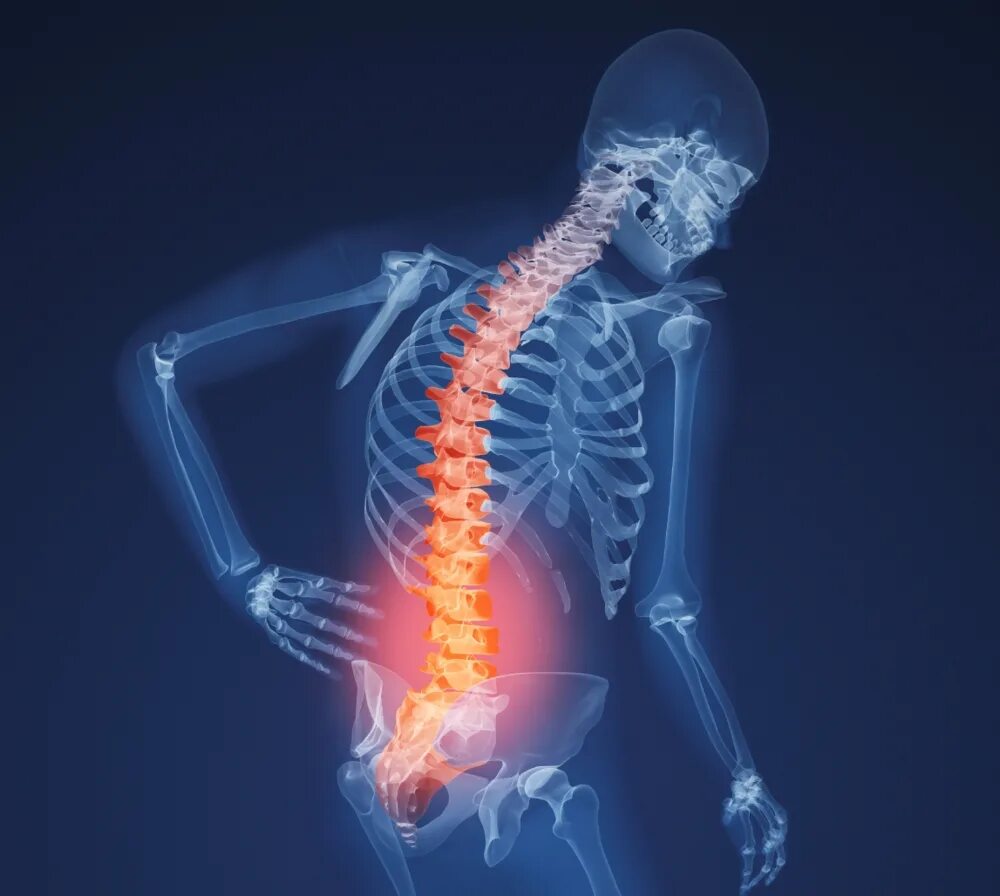

Backbone s